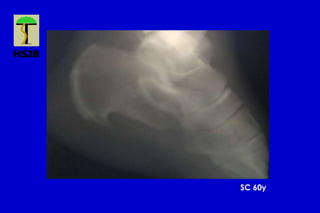

Talalgias

SC 60y

Incidencias radiológicas